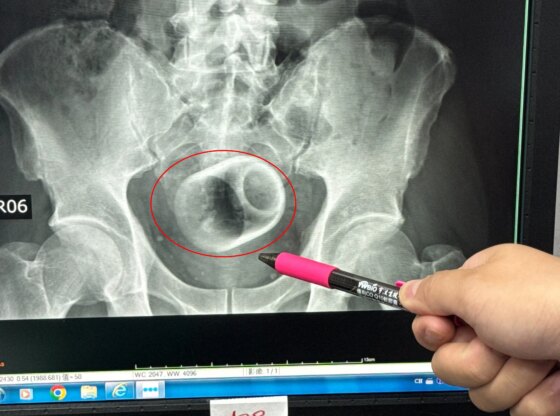

An X-ray revealed there was a ceramic cup inside him.

Measuring around 6cm wide and 8cm tall, medics tried to remove the piece of crockery.